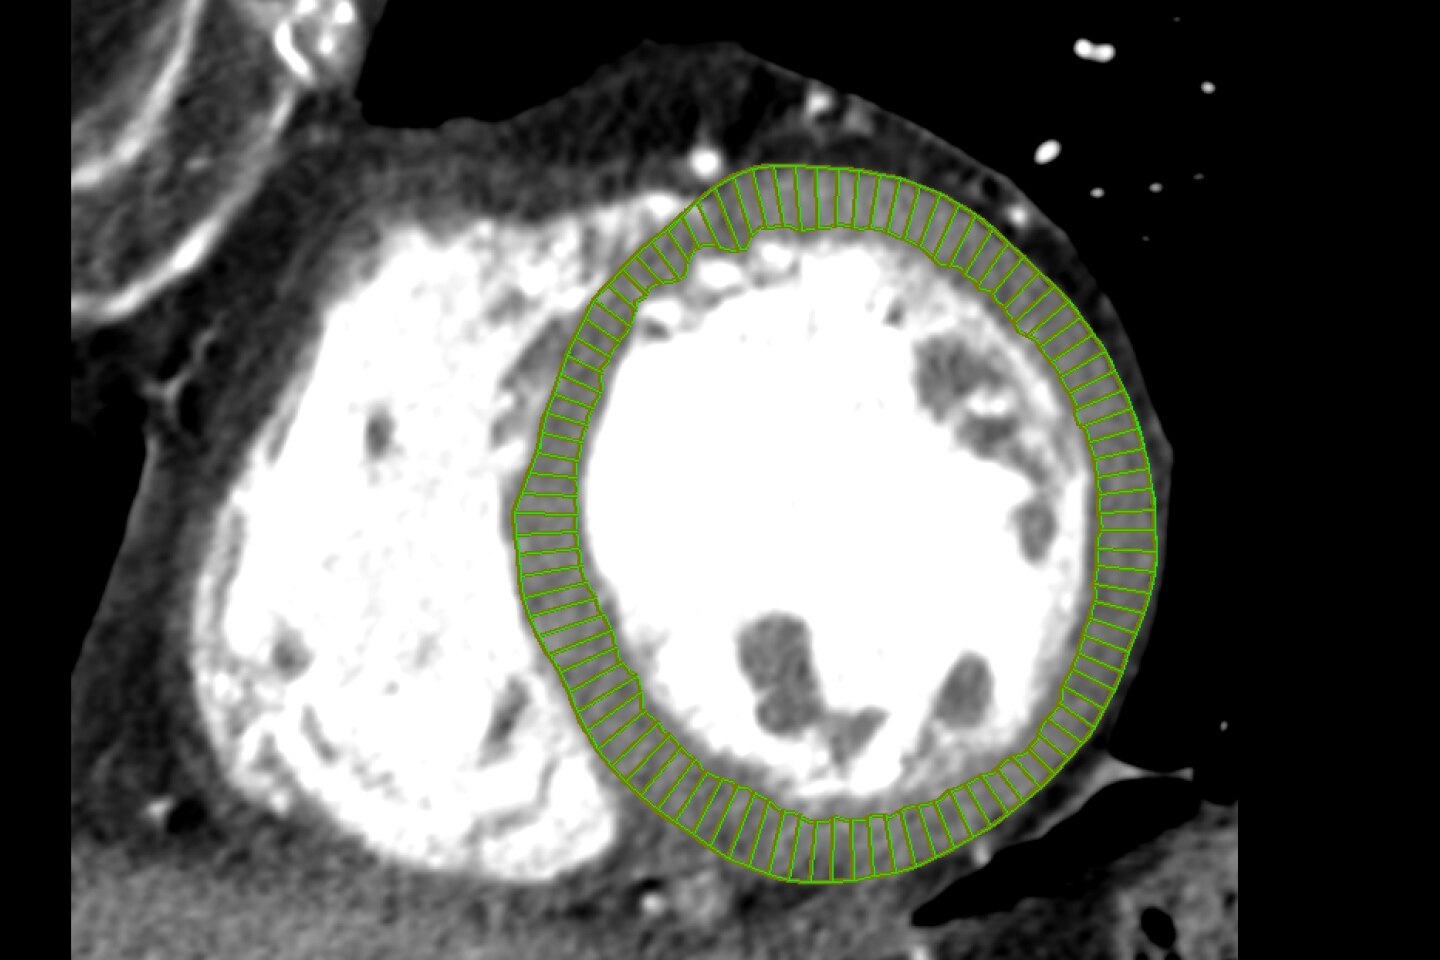

Voyez plus grand durant vos interventions chirurgicale. Grâce à une reconstruction par 19 x 19 x 19cm, l'OEC 3D reconstruit un volume 67% plus grand que les systèmes concurrents*.

Un diagnostic précis

L'OEC 3D tire partie de la technologie de reconstruction AW de GE HealthCare, permettant de tirer le maximum de l'imagerie 3D. Vous pouvez analyser les images et les volumes grâce aux outils du Volume Viewer, incluant le mode multi-oblique, la navigation à travers les 512 coupes, le fenêtrage ou le zoom.